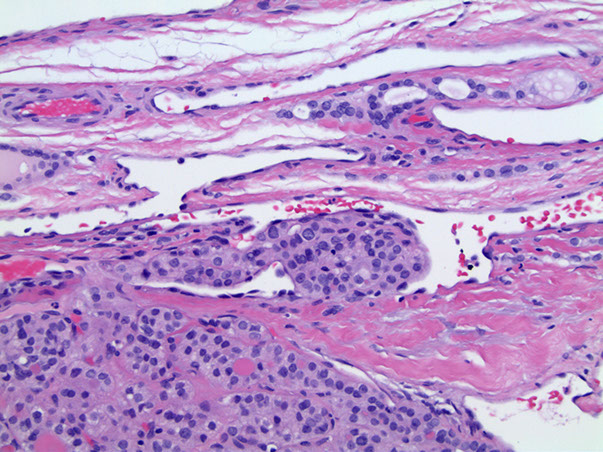

minimally invasive follicular ca

Lymphovascular invasion - minimally invasive follicular ca

Follicular Carcinoma

Micro:  uniform follicules c colloid (like normal thyroid); cannot differentiate a follicular carcinoma from a follicular adenoma based purely on cytology, but need to see an invasive component (in or through capsule or vascular invasion) or distant mets

- look out for vascular invasion (in our outside of capsule) that is attached to the BV wall

-- tumors plugging the BV may become endothelialized